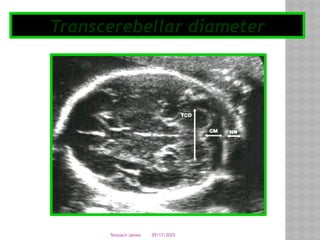

TRANSCEREBELLAR DIAMETER

 When composite biometry is not consistent in all of the

parameters (i.e. BPD, head circumference,

abdominal circumference, femur length), using the

transcerebellar diameter is a way to more accurately

date a pregnancy

 The diameter in millimeters corresponds

to weeks of gestation up to 24 weeks.